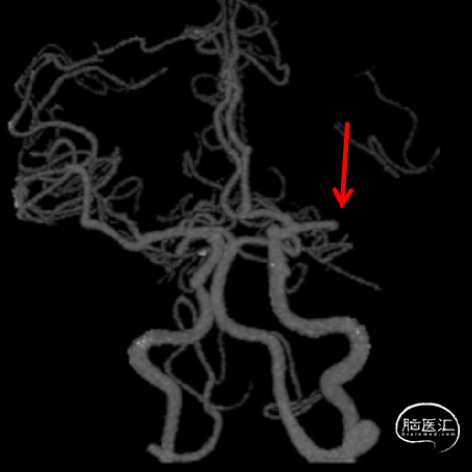

DSA

1、急性脑梗死。2、左侧大脑中动脉M1段闭塞。

ICAS合并血栓?

夹层合并血栓?

栓塞?

微导管通过后,结合首过效应、支架释放效应等决定取栓及后续策略。